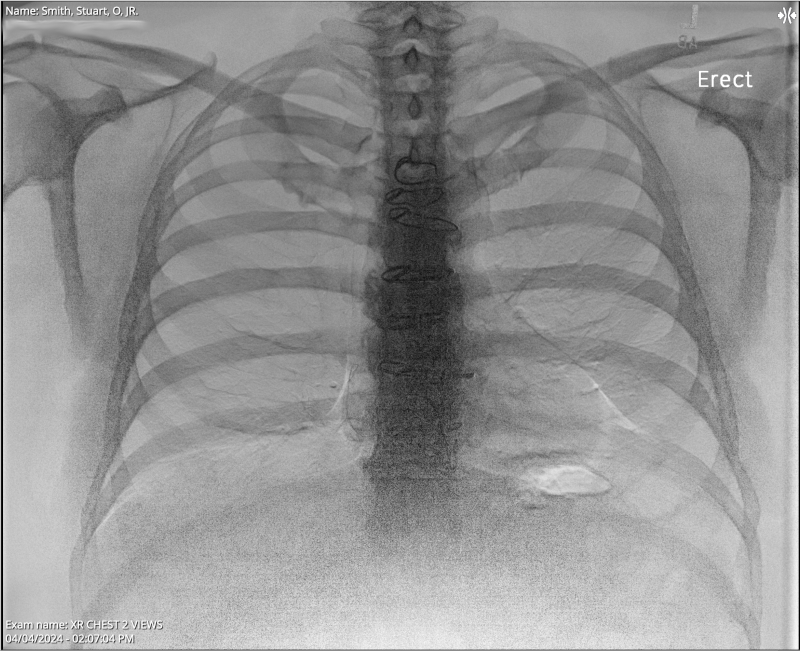

Chest X-ray

XR Chest 2 view Collected on April 5, 2024 7:42 PM . . . Impression 1. No evidence of acute cardiopulmonary process. . . . ORDERING CLINICIAN: EIRAN GORODESKI FINDINGS: Median sternotomy wires present. CARDIOMEDIASTINAL SILHOUETTE: Cardiomediastinal silhouette is normal in size and configuration. LUNGS: Lungs are clear. ABDOMEN: No remarkable upper abdominal findings. BONES: No acute osseous changes.

The results from my April 4, 2024, chest x-ray looked good. I still find it strange to view my x-rays and see some of the hardware that was left inside me after my April 27, 2023, septal myectomy (open-heart surgery) for Hypertrophic Cardiomyopathy. The notes above mention "Median sternotomy wires present," plus I also have retained epicardial pacing wires left inside me, which I have seen in other x-rays.

If you look very closely at the x-ray photo at the top of this blog post, and the following two x-ray photos, you can see the sternotomy wires:

As my appointment with Dr. Abu-Omar proceeded, I learned that my assumption about the appointment was completely wrong. I learned that while it is very rare, chest pain like mine can sometimes be caused by the sternal wires that were left in my body after the surgery. (To the right I added for a second time the same X-ray photo from April 4, 2024, that clearly shows the median sternal wires, and a close-up photo taken from the June 6, 2024, CAT Scan.)